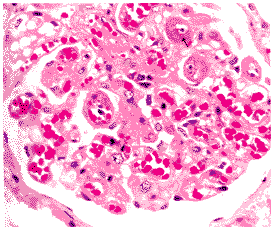

光鏡檢查肝結構完整,肝細胞無明顯炎症或變性表現,僅在肝小葉中央區有些膽小管內可見膽檢,膽小管直徑正常或有輕度擴張。小葉中央區的肝細胞含有色素,並可見嗜鹼性的顆粒聚集。由於病變不明顯有時可被忽略。

電鏡檢查

細胞一般結構完整,線粒體大小、電子密度及其分布均正常,粗面內質網、核糖體及糖原的外形和分布亦屬正常;光滑內質兩輕度擴張,其主要病理表現在肝細胞的膽管極,溶酶體數量輕度增加,圍繞毛細管的外胞漿區增寬,毛細膽管有不同程度的擴張,微絨毛扭曲、水腫或消失。管腔內充滿顆粒狀的緻密電子物質(可能為膽汁)。